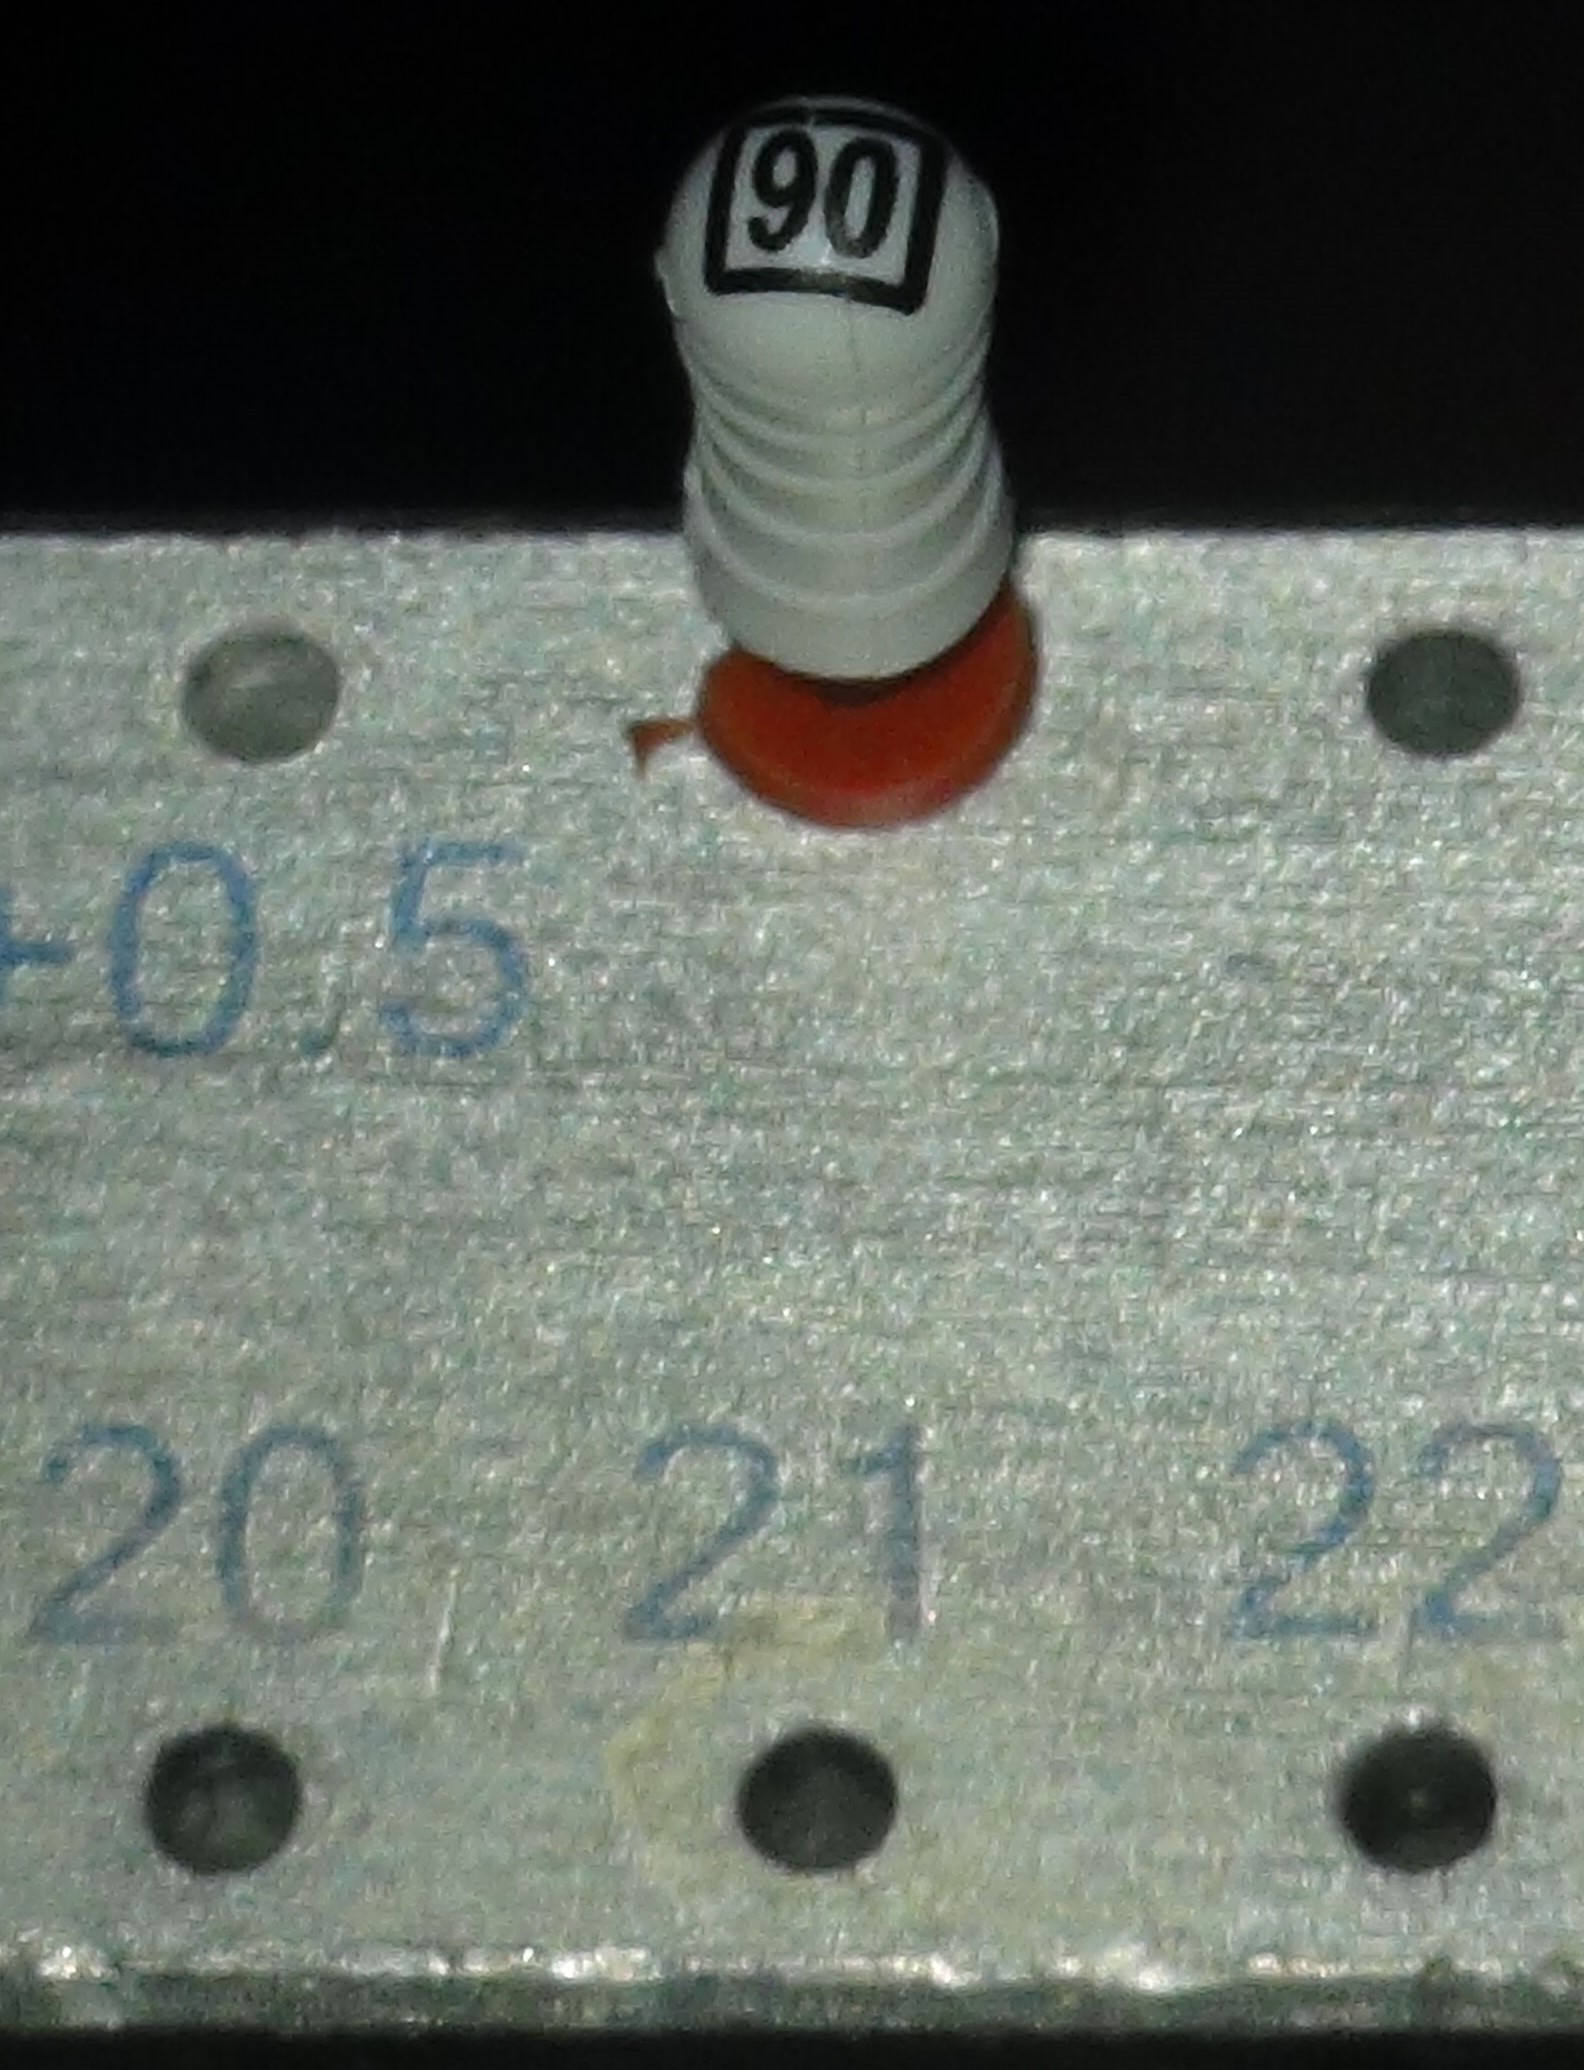

We gaan over tot herbehandeling van element 21. En waar we in 2006 nog een apicale opening aantroffen van ISO 40, loopt nu een vijl ISO 90 net vast bij de elektronisch bepaalde terminus.

We besluiten om hier MTA (Mineral Trioxy Aggregate) te gebruiken. De moeilijkheden om het lastig te verwerken materiaal aan te brengen zijn te overzien. Het element is niet al te lang, in ieder geval 2 millimeter korter dan in 2006, 20,5 in plaats van 22,5 millimeter en door de microscoop kunnen we de uitgang zien. Het enige nadeel van MTA is dat er geen laterale anatomie mee gevuld wordt.